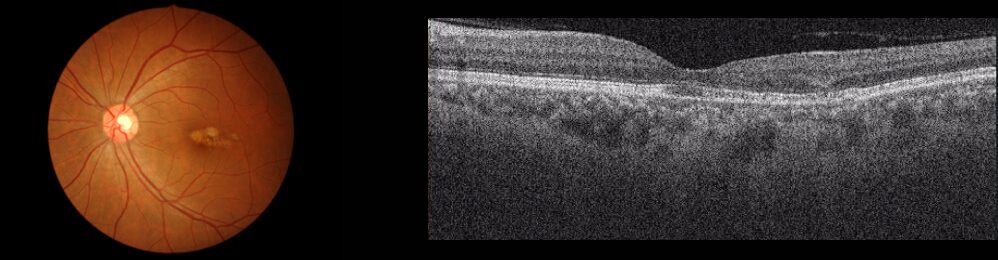

萎縮型

黄斑部ににたまった老廃物が網膜を萎縮させることで起こります。日本人の加齢黄斑変性全体の約1割と滲出型に比べて、少ないです。進行は遅く、視力の低下もゆっくりです。経過観察と生活習慣の改善が望ましいです。